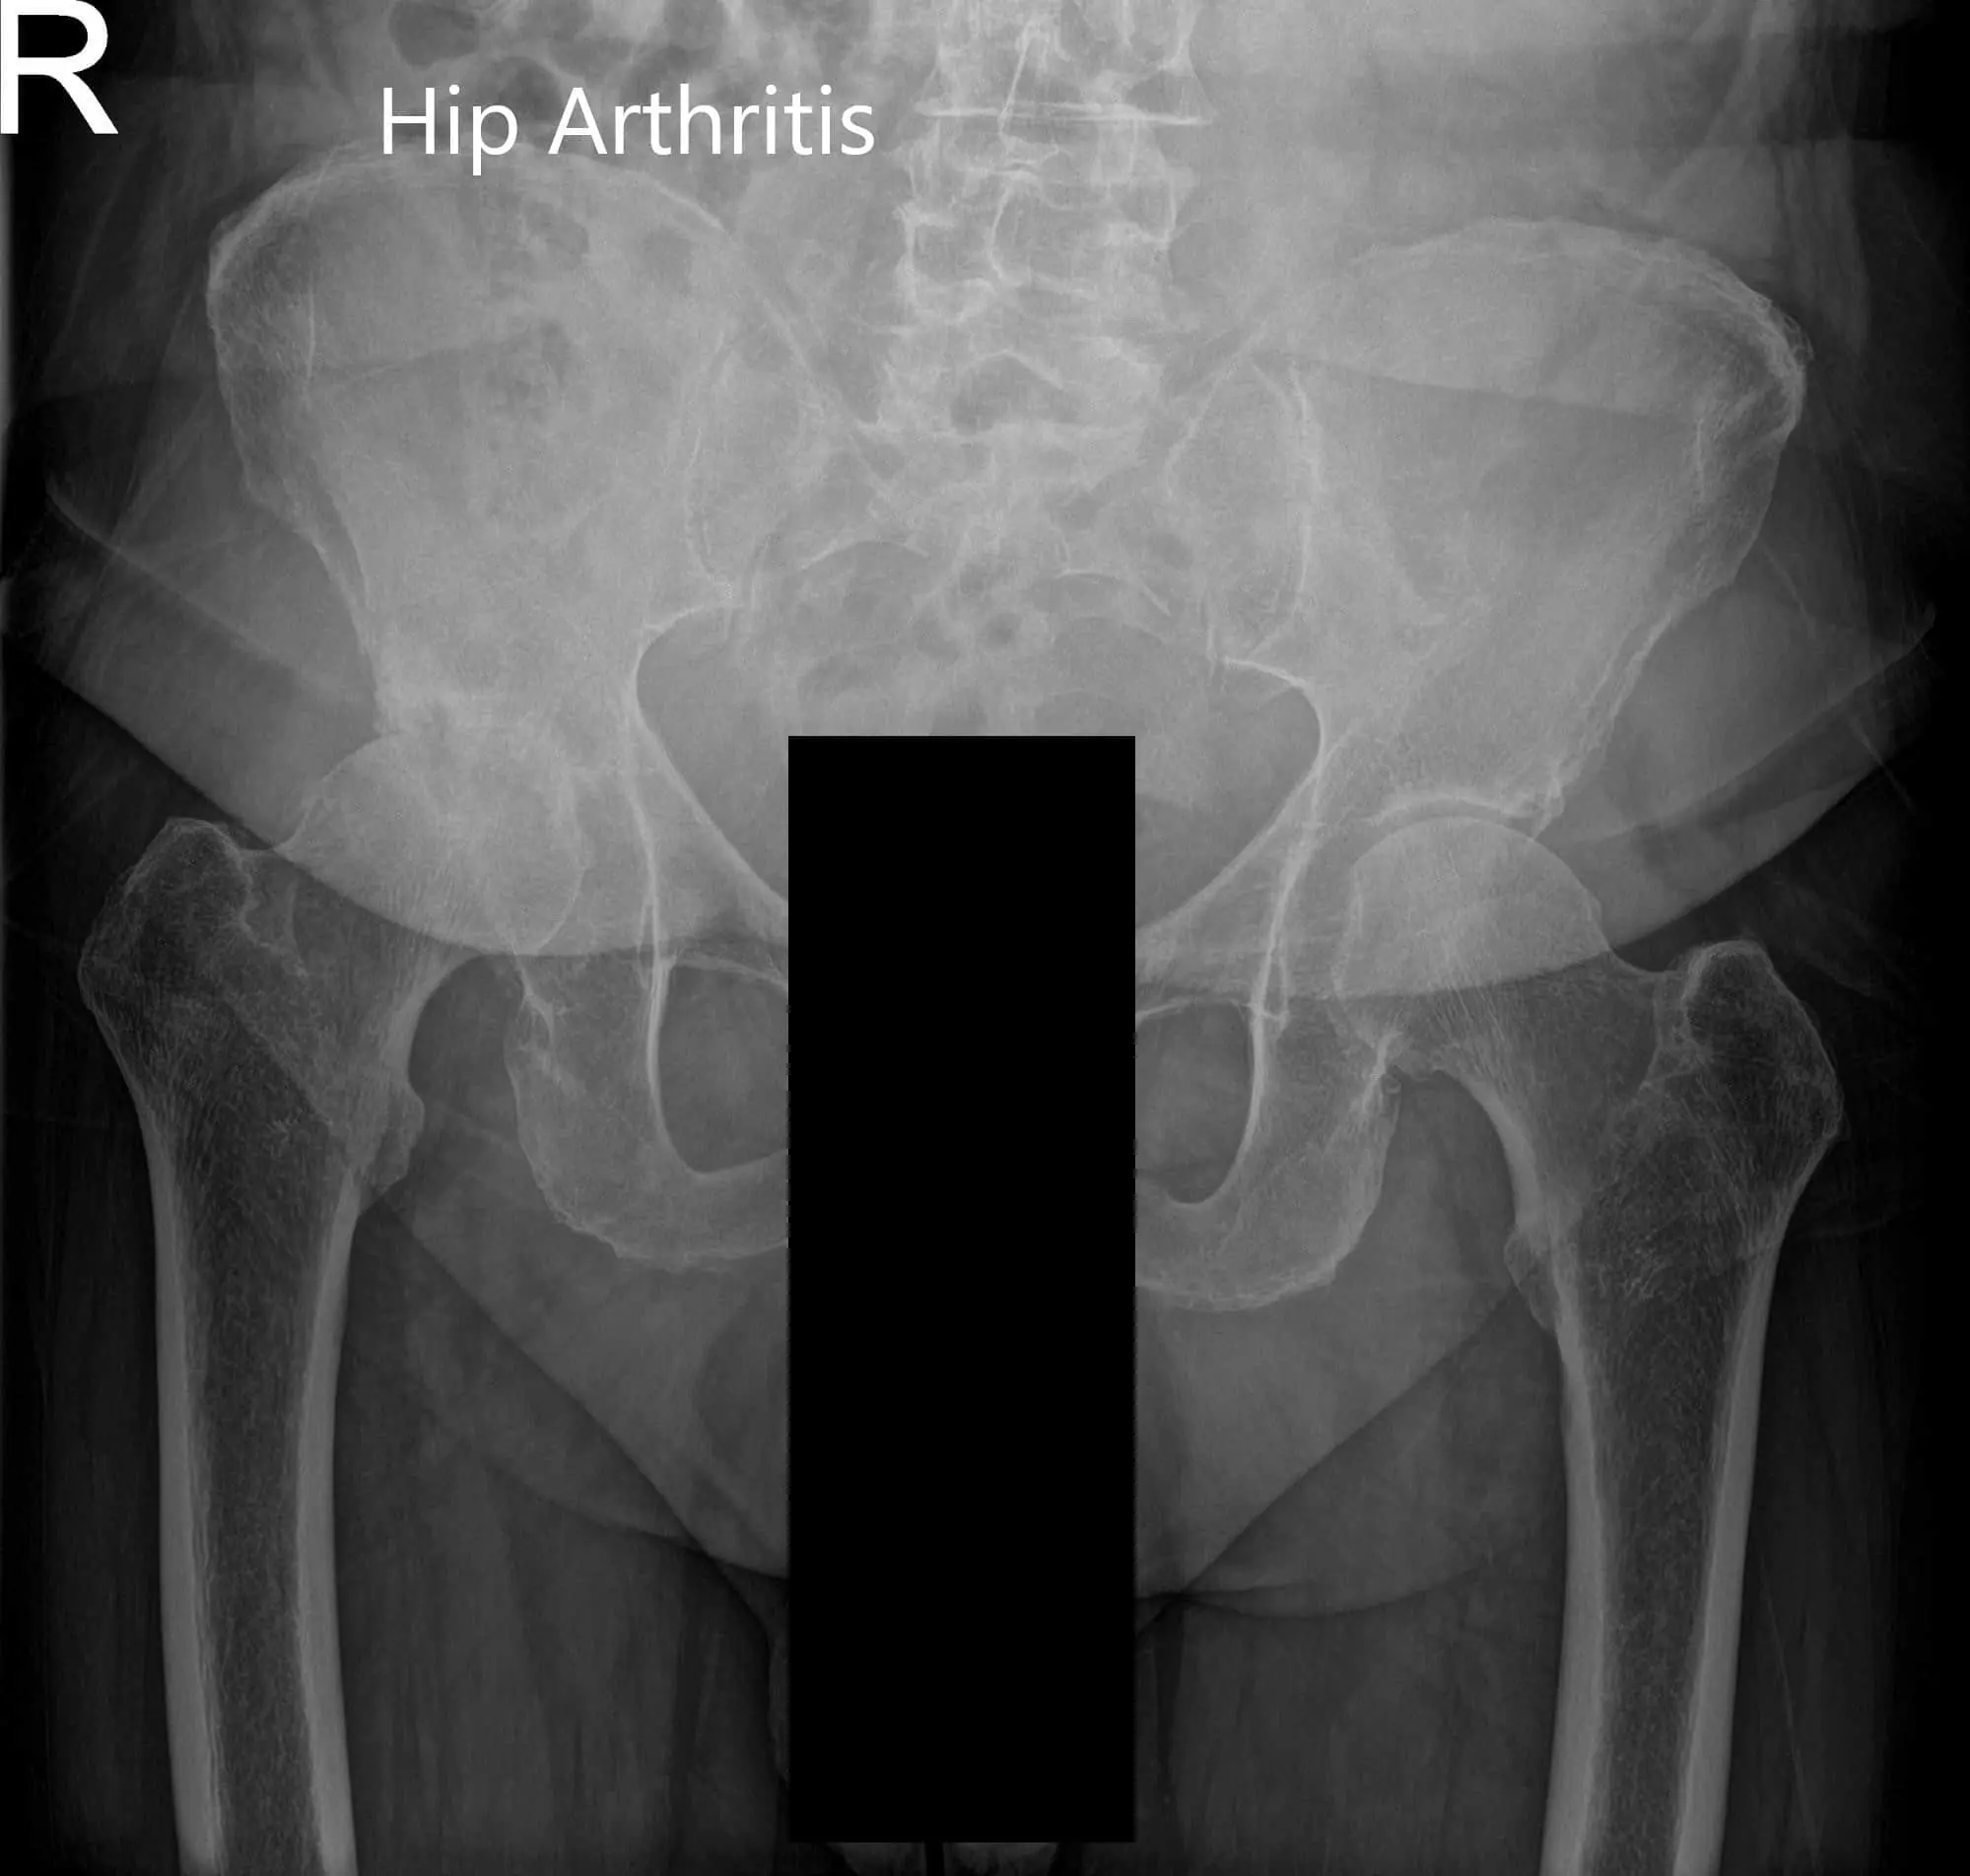

Preoperative X-ray of the pelvis, AP view, and frog-legged lateral view of the right hip.

Preoperative X-ray of Pelvis AP view and frog-legged lateral view of the right hip (image 2)